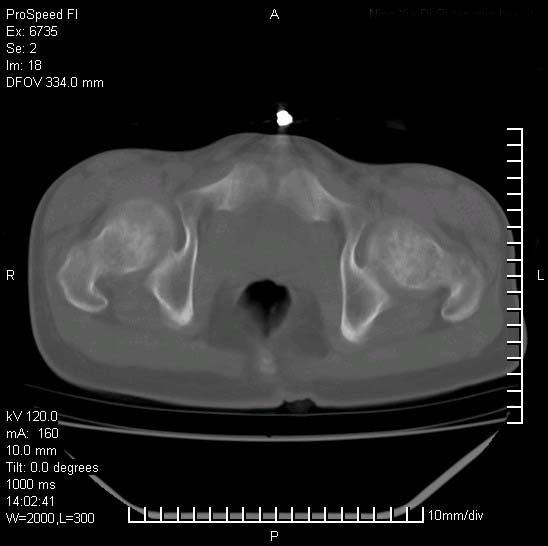

患者自诉胯部疼痛两年余,在当地服用中药,半月前至本院考虑骶髂关节结核,给予抗痨治疗。现发展至右下肢疼痛明显,活动受限,以膝关节处明显,拍膝关节平片无明显异常。

两侧骶骼关节改变,考虑强直性脊炎

左侧骶髂关节面限局性骨破坏,边缘硬化关节腔见钙化物;不出外tb

右侧骶髂关节也有类似改变,只是较左侧轻,首先考虑强直性脊柱炎,不除外结核,建议作hla-b27检查。

典型强脊炎改变,髋关节亦有累及

符合强直性脊柱炎表现。